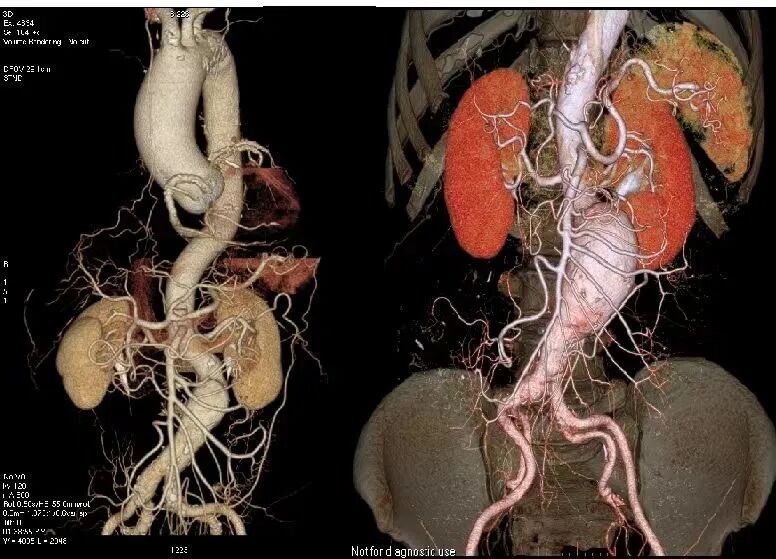

对比传统CT检查一个部位需要注射一次造影剂,Revolution CT可以注射一次造影剂,一次性完成冠状动脉CTA、肺动脉CTA及主动脉CTA等多部位CTA检查,得到高对比度的影像图,不仅安全,还省心省力省时更省钱。

16cm宽体等焦宝石DOD探测器,是目前业内最宽探测器,可轻松覆盖心脏、颅脑、肝脏等器官,搭配独有的自由组合一站式联合扫描技术,能够一次性实现多血管或多器官联合扫描。百万像素超高分辨率检查+3mm超低密度分辨率,将小病灶显示得更清楚、边界更清晰。大幅提高检查效率和成像效果,有效协助医生进行精准诊断和全面诊断。